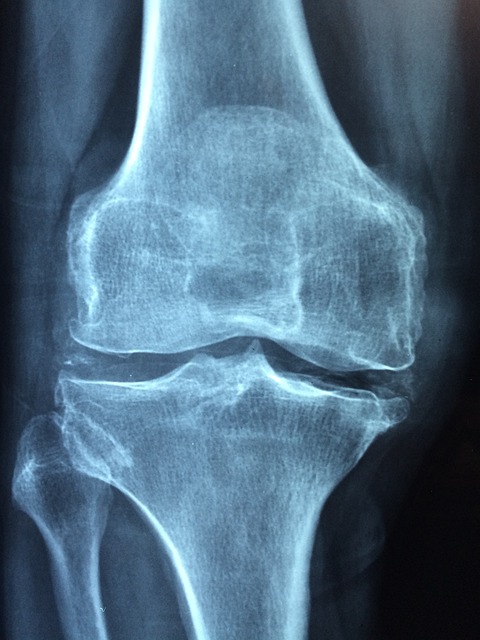

- X-ray 검사 – 연골이 마모되었거나 뼈가 자란 증상(골극, Bone Spur) 확인 가능.

- MRI 검사 – X-ray로 보이지 않는 연골과 연조직 손상을 더 정밀하게 검사.